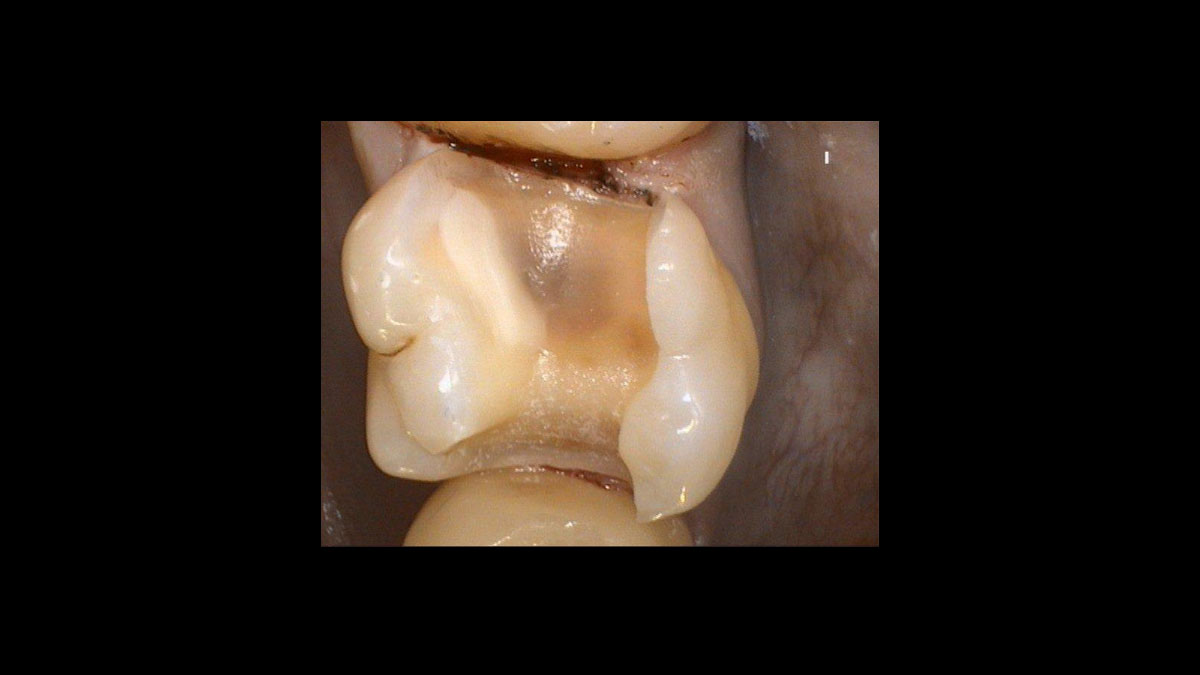

Réduction des germes parodontiques